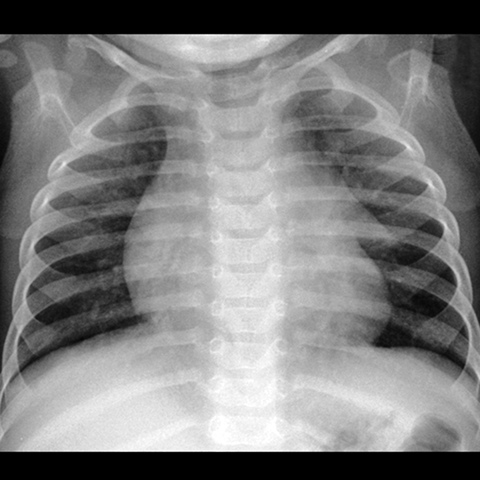

Thymus, Normal Infant (CXR) [1 of 2]